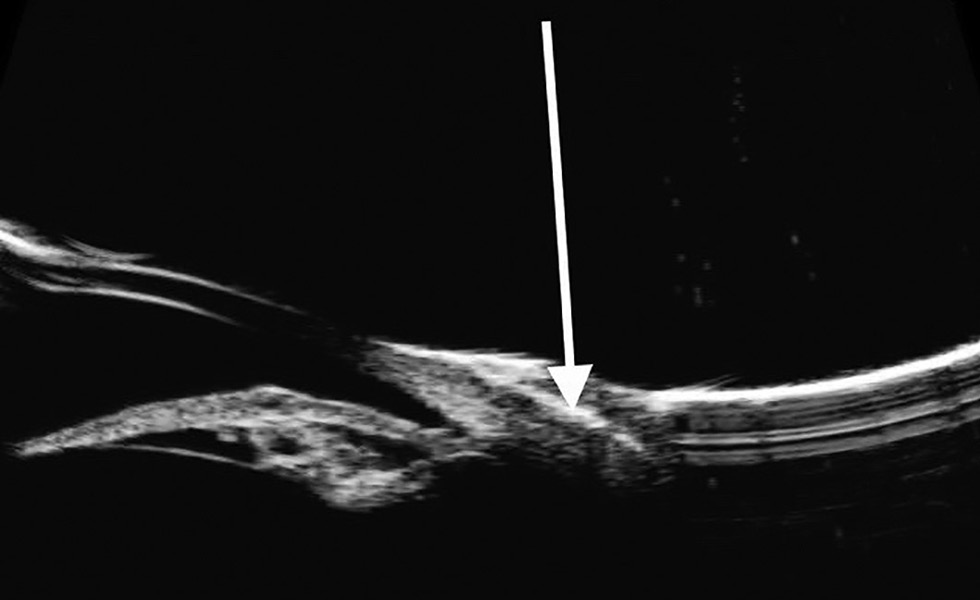

С помощью УБМ была выявлена фенестрация и резорбция слоя клеевой плёнки, полное закрытие склеры новообразованной конъюнктивой, которая была утолщена до 0,5 мм. По данным ОКТ наблюдалось снижение выраженности проминенции конъюнктивы в области трансплантации относительно здоровых тканей (рис. 4).

Рис. 4. Оптическая когерентная томография на 21-е сутки после операции: 1 — роговица, 2 — радужка, 3 — конъюнктива в области операции.

Fig. 4. Optical coherence tomography on Day 21 post-surgery: 1, cornea; 2, iris; 3, conjunctiva in the area of surgery.